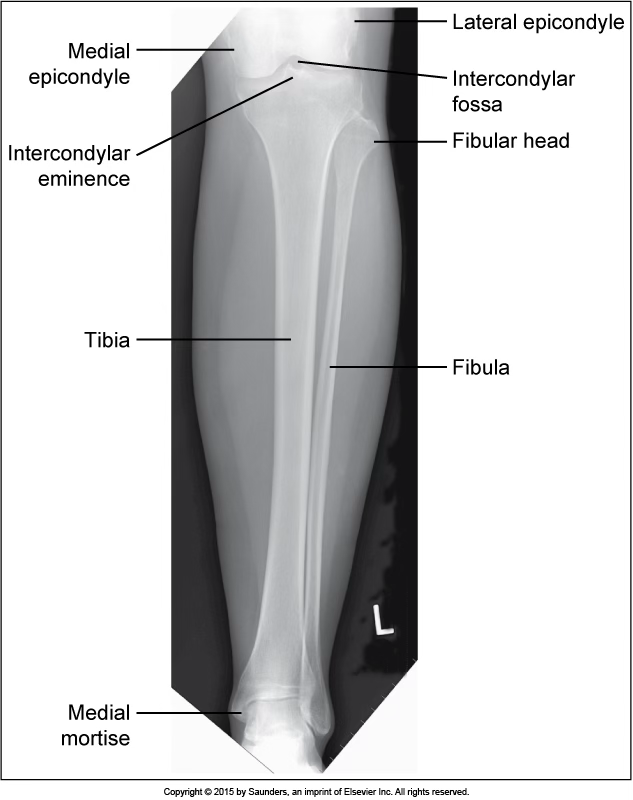

AP tibfib

accurate positioning

lateral tibfib